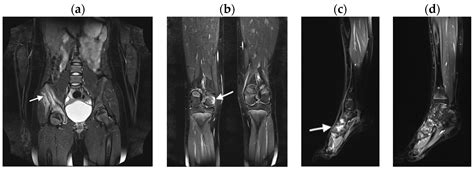

The lesions most commonly appear in the metaphyses of long bones, the pelvis, the vertebrae, and the clavicle. The "multifocal" aspect of the name refers to the fact that these lesions can appear in several locations simultaneously or develop sequentially over time, leading to a frustrating cycle of remission and flare-ups that can last for years.

Diagnostic Approach and Imaging

Diagnosing Chronic Multifocal Osteomyelitis is a process of exclusion. Because there is no single laboratory blood test that confirms the diagnosis, physicians rely on a combination of clinical findings, imaging, and, in some cases, a bone biopsy to rule out other more serious conditions like malignancy or bacterial osteomyelitis.

MRI (Whole Body) The gold standard for identifying multifocal lesions without radiation exposure.

💡 Note: A whole-body MRI is highly recommended by specialists to identify asymptomatic lesions that might otherwise go undetected.